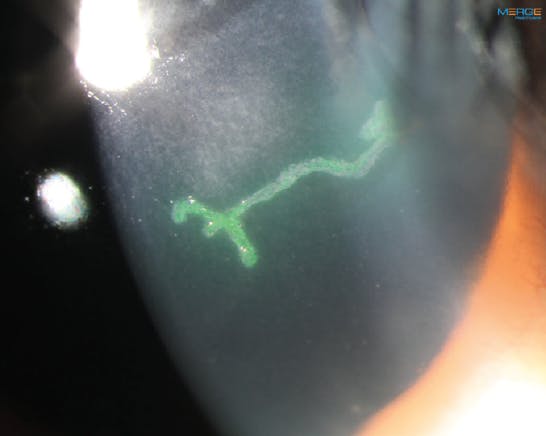

Epithelial HSV may present as the classic dendrite with terminal bulbs or geographic lesions. The geographic ulcers are sometimes hard to differentiate from a healing corneal abrasion with irregular borders or neurotrophic keratitis. However, the bodies of both dendrites and geographic lesions stain with fluorescein (Figure 1), and the edges stain with lissamine green or rose bengal. This is not the case with abrasions or neurotrophic disease.

The main question in determining treatment is whether this is an active replicating virus or largely an immune response. With epithelial disease, it is mainly viral replication, and it is contraindicated to start the patient on a topical steroid. The Herpetic Eye Disease Study found that with topical or oral antiviral treatment, epithelial disease typically resolved within 2 weeks (Figure 2).2 If epithelial disease lasts more than 14 days or does not appear to be improving with topical treatment, the clinician should suspect that the topical antiviral is causing toxicity to the ocular surface and switch to an oral antiviral. If the patient is taking only an oral antiviral and epithelial disease is not resolved within 14 days, one should then consider a different diagnosis. Another treatment option is debridement to lessen the viral load and accelerate resolution.